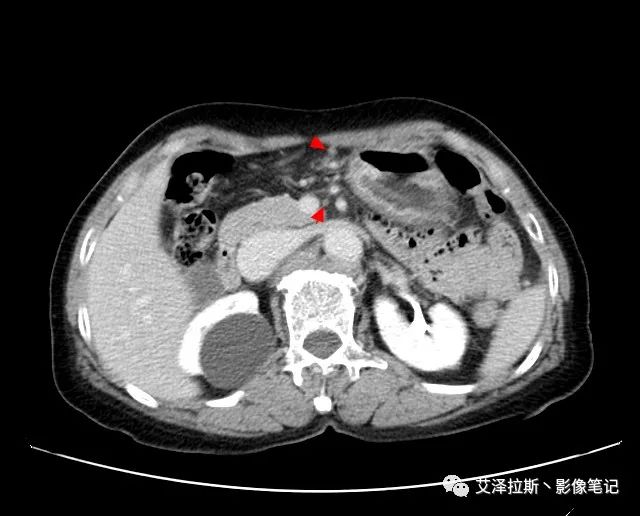

【基本情況】 患者,女性,66歲,貧血。

圖1 平掃+增強各期

【影像所見】 胃竇部狹窄,胃壁環形增厚,小彎側見一巨大潰瘍,周圍伴“環堤征”,漿膜面不完整,胃周脂肪見網格狀條索影,病灶與肝臟左葉、胰腺鉤突脂肪間隙消失,增強掃描病灶明顯強化。引流區內約15個區域淋巴結受累。

【診斷意見】 胃竇部胃癌(T4N3期) 該病例腫塊突破漿膜層,與肝臟左葉、胰腺鉤突分界不清,脂肪界面消失,定為T4期; 受累及的淋巴結為15個區域,定為N3; 有無遠處轉移尚不明確,所以M期暫時無法確定。